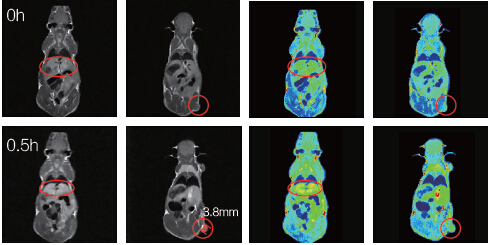

利用1T-MRI可以實現小鼠生理特征的定量計算,包括組織體積、腫瘤的尺寸、造影效果定量化評價等;MRI方法無需處死老鼠,簡單快速,提高了實驗結果的可靠性、實驗速度與實驗的連續性。

小鼠腫瘤直徑3.8mm;打入新型Mn螯合造影劑0.5h之后,通過灰度平均值計算,發現肝臟與腫瘤造影明顯。